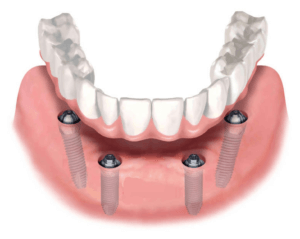

Например, несъемный покрывной протез для имплантации по технологии All-on-4, заменяет полную съемную конструкцию. Главное преимущество — надежное прикрепление к челюсти. Человек может полноценно жевать и разговаривать без стеснения.